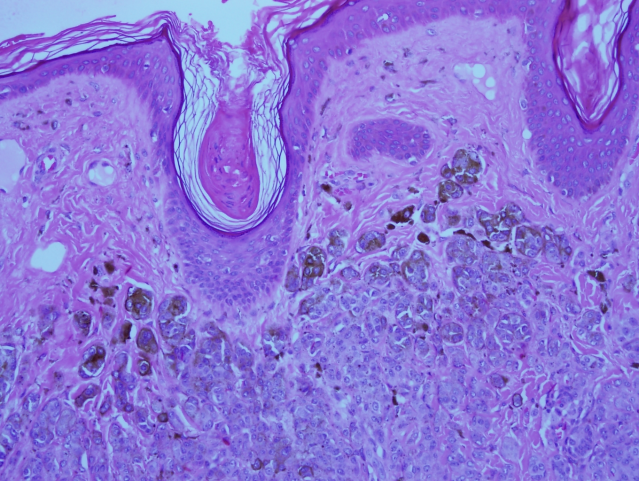

All the specimens collected were sent to the histopathology lab and the report revealed that the specimens had nests and diffusely cellular sheets of benign melanocyte with superficial focal pigmentation and deep dermal maturation. Lateral margins and deeper margins were involved. Overall, there was no malignancy reported (Figure 8 [Fig. 8], Figure 9 [Fig. 9]).

Figure 8: Higher power shows dermal nests with marked adnexocentricity, in addition to infiltrating between the collagen bundles.